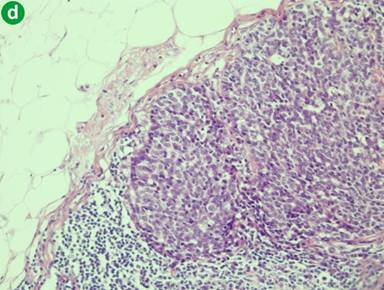

Figure 2. a. On high power magnification, the neoplastic cells are arranged in well defined solid nest and rosettes with oval vesicular nuclei containing occasional prominent nucleoli. Areas of necrosis are present. b. Tumour cells show strong immunohistochemical detection for synaptophysin. c. Large cell neuroendocrine carcinoma of the ampulla of Vater (top left of field), which is adjacent to a residual villous adenoma of the ampulla with low grade dysplasia (bottom of field). d. Regional lymph node metastasis. Magnifications: 200x, 200x, 20x, and 200x for a., b., c., and d., respectively). |

The patient presenting at our institution (Table 1; AMNCH case) had a villous adenoma associated with the LCNEC (Figure 2c). An associated adenoma was also found in 4 of the reported cases in the literature. The median survivals approximate 15 months for those with associated adenoma and 11 months without. This is not a statistically significant difference (Figure 3; Log rank P=0.420).

Lymph nodes were positive for metastases in 15 out of 17 cases (88.2%; Figure 2d), with a mean number of 2.2 nodes involved. The Ki-67 index was recorded in 4 cases, ranging from 41 to 90%. The commonest site of distant metastasis was the liver, with 8 out of 10 cases (80.0%) with recorded metastatic status being positive for liver metastasis. Other documented sites of metastasis were the peritoneum and bone.